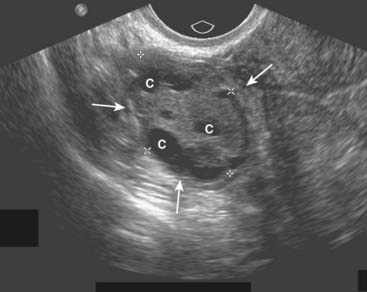

Figure 19-20 Polycystic ovarian disease.

Polycystic ovarian disease is an endocrine abnormality that allows for numerous ovarian follicles (>12 per ovary) to develop in various stages of hormonal growth and atresia. This ovary (O) is enlarged (solid white arrows) and contains multiple peripheral cysts, some of which are labeled (C). When associated with oligomenorrhea, hirsutism, and obesity, polycystic ovarian disease is called Stein-Leventhal syndrome.